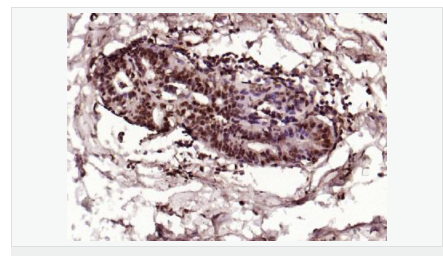

交叉反應(yīng):Human,Mouse,Rat(predicted:Dog,Pig,Rabbit,GuineaPig) 推薦應(yīng)用:IHC-P,IHC-F,ICC,IF,Flow-Cyt,ELISA

| 產(chǎn)品應(yīng)用 | ELISA=1:5000-10000 IHC-P=1:100-500 IHC-F=1:100-500 Flow-Cyt=1μg/Test ICC=1:100 IF=1:100-500 (石蠟切片需做抗原修復(fù)) not yet tested in other applications. optimal dilutions/concentrations should be determined by the end user. |